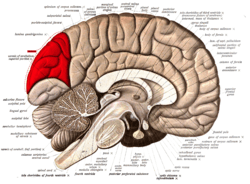

![]() Medial surface of left cerebral hemisphere. (Cuneus visible at left in red.) | |

The cuneus (Latin for "wedge"; plural, cunei) is a smaller lobe in the occipital lobe of the brain. The cuneus is bounded anteriorly by the parieto-occipital sulcus, inferiorly by the calcarine sulcus.